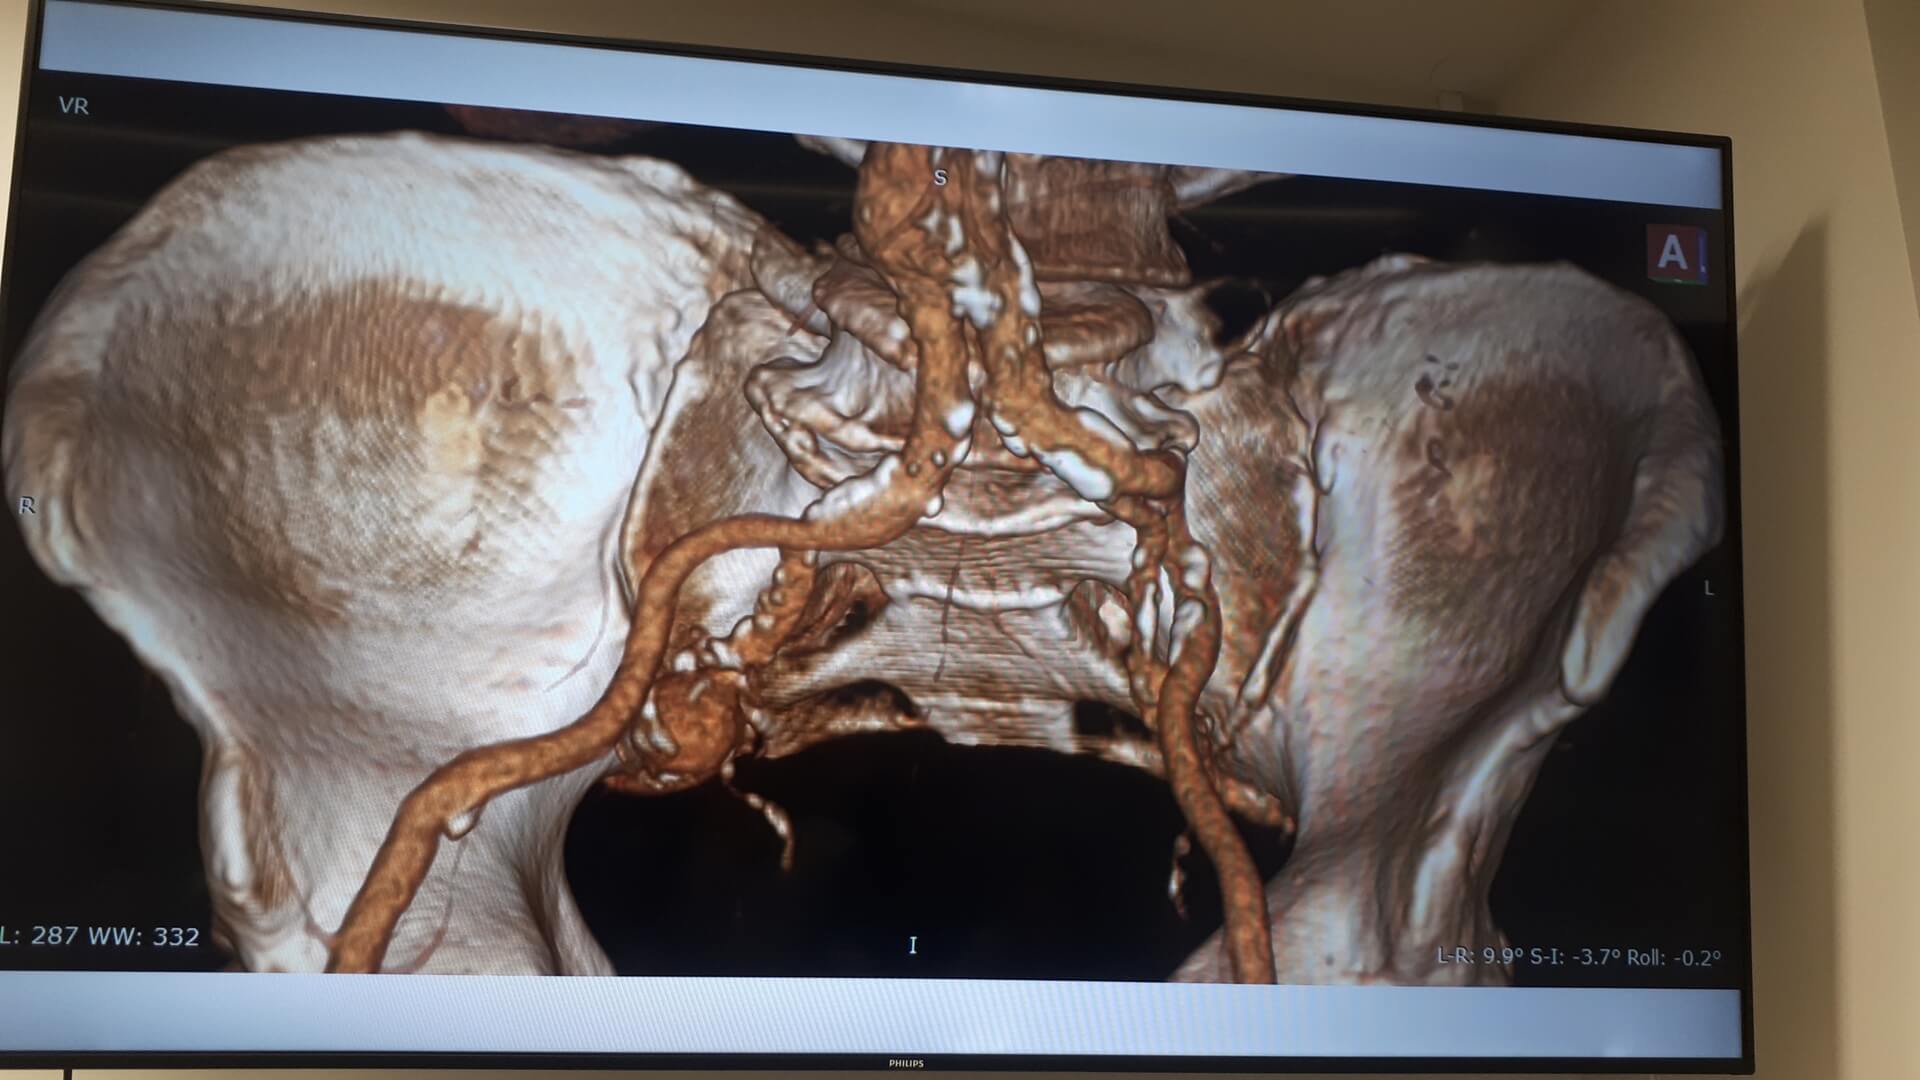

Pierwszą w Polsce operację wszczepienia nowego rodzaju stentgraftu, czyli specjalnej protezy do zabezpieczania tętniaków aorty, przeprowadzili lekarze z Uniwersyteckiego Szpitala Klinicznego w Białymstoku.

Chodziło o tętniaka tętnicy biodrowej u 64-letniego pacjenta. Operację przeprowadzono w minioną środę (10.04) w Klinice Chirurgii Naczyń i Transplantacji USK. Pacjent czuje się dobrze i niedługo wychodzi ze szpitala.

Jak mówił w czwartek (11.04) na konferencji prasowej kierownik tej kliniki dr hab. Jerzy Głowiński, tętniak miał prawie 4 cm, co w relacji do wielkości tętnicy biodrowej wewnętrznej stanowiło duże zagrożenie, bo w każdej chwili ścianki naczynia krwionośnego mogły pęknąć, powodując – zagrażający życiu – krwotok wewnętrzny. - Możliwości uratowania byłyby naprawdę znikome – powiedział.

Rozwiązaniem okazał się nowy rodzaj stentgraftu, czyli specjalnej protezy wszczepianej do tętnic. "Jest to stentgraft, który jest jednocześnie i miękki, i na tyle sztywny, że się do tego celu dobrze nadawał" – powiedział. Zwrócił przy tym uwagę, że stosowane już standardowo stentgrafty są albo sztywne, albo elastyczne i do zabezpieczenia tętniaka w takim miejscu się nie nadawały.

DrJerzy Głowiński wyjaśniał, że tętnica biodrowa jest stosunkowo mała i kręta, do tego jej średnica nie jest na całej długości taka sama. Nowy rodzaj stentgraftu składającego się z pierścieni naprzemiennie sztywnych i elastycznych dał możliwość "domodelowania" go w taki sposób, by na całym zabezpieczanym tętnicy odcinku był właściwie zainstalowany.